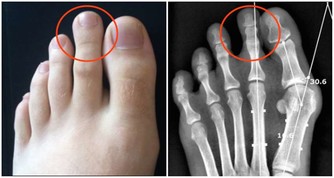

3. 你的腸道裡有寄生蟲

大便中的白色斑點也可能是絛蟲或蟯蟲。雖然如今絛蟲感染並不常見,但依然有可能。如果看到白色或黃色的斑點,可能就是絛蟲,它們通常是扁平的、方形的,大小與米粒相當。有些人可能沒有症狀,但有些人可能出現胃痛或腹瀉。人們通常是因為吃生的或未煮熟的肉而感染絛蟲。絛蟲感染比較好治療,一粒藥丸就足以殺死絛蟲,它會從糞便中排出體外。

大便上出現白點,是什麼原因造成的?

蟯蟲感染更常見,特別是在兒童中。蟯蟲很小,是白色的,大小和訂書針一樣大。

它們通常看起來像白線,所以也被稱為線蟲。

蟯蟲通常生活在腸道的下部,並在肛門周圍的皮膚上產卵,這可能會導致肛門不適和瘙癢。